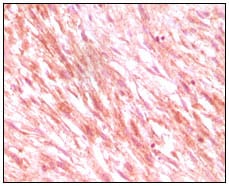

- Immunohistochemical analysis of paraffin-embedded human prostate tissues using GSTP1 mouse mAb with DAB staining.